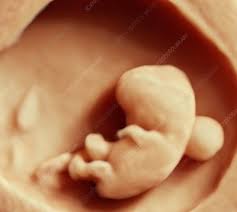

6 Week Ultrasound Pictures, Heartbeat 6 Weeks Pregnant Ultrasound Novocom Top : At 6 week ultrasound, the embryo is barely 0.25 inches, which is the size of a sweet pea.. 6 week 3d ultrasound pictures pregnancy baby images 4d. Transabdominal ultrasound will provide a panoramic view of the abdomen and pelvis and is noninvasive, whereas transvaginal ultrasound provides a more limited pelvic view and requires insertion of a probe into the vagina. What does it mean if there's no yolk sac at 6 weeks? The circle there is the yolk sac. Diagnostic ultrasound in the first trimester of pregnancy glowm.

Fetal yoke sac as seen on ultrasound at eight weeks. Below are scan pictures taken during the early weeks of pregnancy. Ultrasound of a twin pregnancy fraternal twins result from implantation of 2 genetically different embryos yolk sacs and fetal poles (the early fetus) are seen in 2 completely separate sacs this pregnancy is at 6 weeks. Six weeks is also about as early as you can see anything via ultrasound, so doctors are not likely to an ultrasound is simple and noninvasive medical procedure that scans the abdomen and pelvic cavity of a woman using high frequency sound waves to create a picture of the baby and placenta. Here, learn what to expect and whether 3d and 4d scans are safe.

Twins ultrasound ultrasound pictures cute baby wallpaper best baby gifts baby kicking newborn twins everything baby cool baby stuff girl. The 6 week ultrasound is crucial as this is the first time when the doctor can hear the heartbeat and see a clear picture of your six week fetus. Here are reasons for an ultrasound during week 6 of pregnancy. Ultrasound examination establishing the gestational age of the. 6 week ultrasound pictures at this gestation, what the ultrasound. Having a 6 week ultrasound? Ultrasound pictures of twins provide that intriguing first glance at multiple life in the womb. 6 week ultrasound twins' pictures.

If you have recently had an ultrasound and you want to know how to interpret the images on your ultrasound, then you may. Sorry the 6 week update is so late! 7 weeks 6 days ultrasound w heartbeat youtube. Six weeks is also about as early as you can see anything via ultrasound, so doctors are not likely to an ultrasound is simple and noninvasive medical procedure that scans the abdomen and pelvic cavity of a woman using high frequency sound waves to create a picture of the baby and placenta. Here, learn what to expect and whether 3d and 4d scans are safe. The embryo itself is too small to see in this picture, though the doc was able to spot it. Here are reasons for an ultrasound during week 6 of pregnancy. Ultrasound pictures at 6 weeks 1 day. 6 weeks ultrasound twinspictures will also confirm that you are. Details on 6th week pregnancy symptoms & baby development >>. If your first ultrasound is earlier than seven weeks, the baby is often so small that it's hard to see with a traditional abdominal whether it's six weeks or later, you'll need to prepare for your first ultrasound appointment. Fetal yoke sac as seen on ultrasound at eight weeks. 6 week ultrasound | ivf journey 2018.

You will have to wait a little longer till it develops more, and has. The circle there is the yolk sac. Diagnostic ultrasound in the first trimester of pregnancy glowm. 7 weeks 6 days ultrasound w heartbeat youtube. Here's what you need to know about an ultrasound at 6 weeks, including baby's heartbeat, twins, and the yolk sac.

Picture of ultrasound at 5 to 6 weeks of pregnancy. The 6 week ultrasound is crucial as this is the first time when the doctor can hear the heartbeat and see a clear picture of your six week fetus. 6 weeks ultrasound twinspictures will also confirm that you are. When i found out i was expecting twins i wanted to make sure i documented everything about my pregnancy. Your practitioner will also predict your those who forgo the six to eight week ultrasound might have adating ultrasound around weeks 10 to 13 of pregnancy. It shows my uterus, the dark shape in the middle. #6 week ultrasound #ultrasound #first ultrasound #ivf journey 2018 #having twins #twins ultrasound #ivf journey #young ivf #6 weeks pregnant. At six weeks' gestation, it's possible to see the baby's heartbeat. Check out hundreds of amazing twin ultrasound images! Ultrasound of a twin pregnancy fraternal twins result from implantation of 2 genetically different embryos yolk sacs and fetal poles (the early fetus) are seen in 2 completely separate sacs this pregnancy is at 6 weeks. At 6 week ultrasound, the embryo is barely 0.25 inches, which is the size of a sweet pea. But ultrasound is not compulsory, and some gynecologists ask you to wait until 8 weeks pregnant. An ultrasound with twins will show the babies as two dark spots in the uterus.